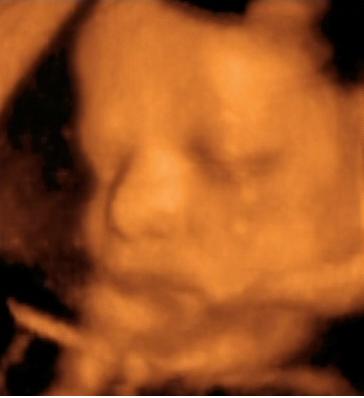

A lényeg. Lányunk lesz. Bár számomra ez nem volt egyértelmű a kép alapján...talán nektek az lesz. Már most kész óriás, 2703 g. Gyönyörű babó, bár most nem voltunk olyan szerencsések, mint a múltkor és folymatosan eltakarta magát. Nagyon fájt a szívem amikor láttam, hogy mennyire össze van "hajtogatva" szegénykém. a bal lába a homlokánál van :(. No de ez van. Remélem azért nem annyira rossz neki.

Küldöm a képeket is.